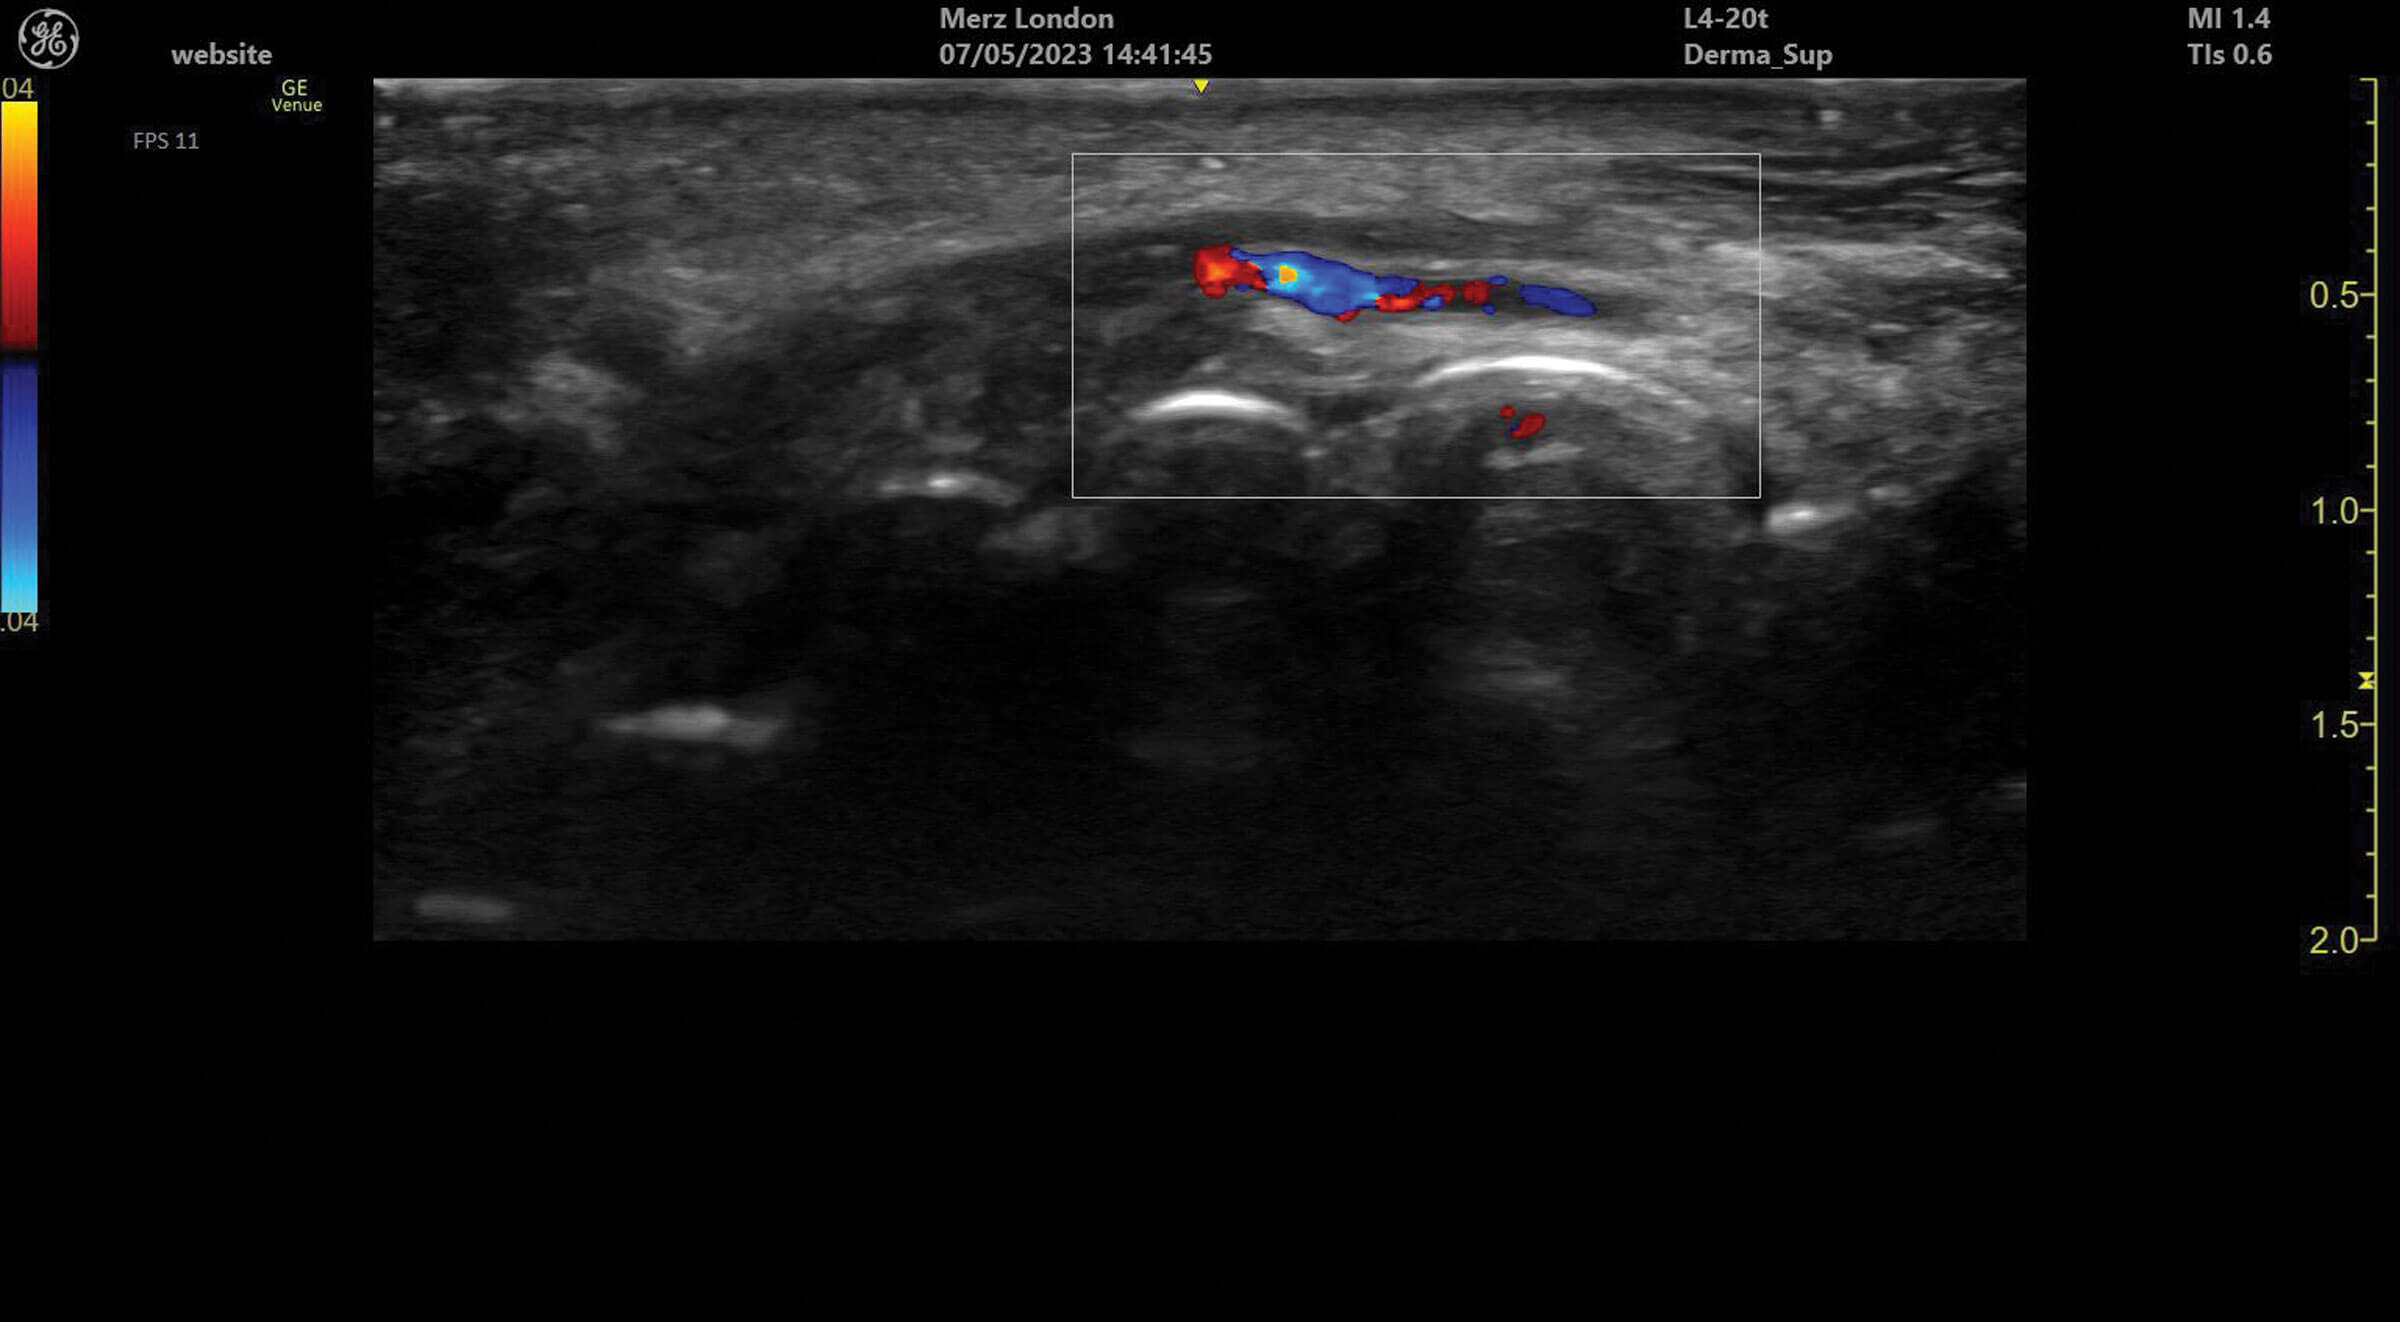

Figure 1: The facial vein and facial artery identified medial to the masseter in the facial plane of the lower face.

Ultrasound doppler can be used to assess blood vessel flow prior to treatments but can also help identify abnormalities in blood supply after filler treatment. Vessels can be identified and tracked in the tissue allowing for the observation of any anatomical variation. Blood vessels always appear as anechoic structures on ultrasound but, when using a colour doppler, flow can be detected either towards (red) or away (blue) from the ultrasound probe [1].